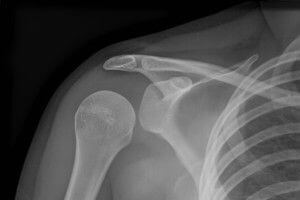

Способы диагностики

Выполняется стандартная рентгенография сустава в 2 проекциях — передней и задней.

Для исключения повреждения лопатки может быть проведена дополнительная рентгенография в боковой проекции.